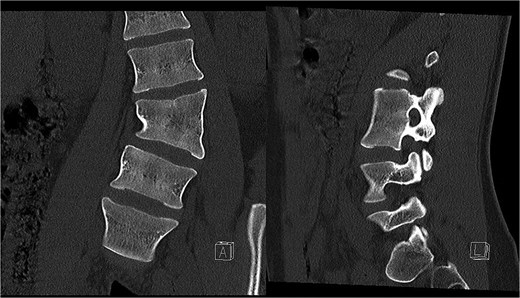

Last preoperative X-ray, lateral (A) and anteroposterior view (B). After 10 weeks of follow-up; lateral (C) and anteroposterior view (D). After 1 year of follow-up; lateral (E) and anteroposterior view (F).

Postoperatively, the patient experienced left psoas and quadriceps femoris muscle paresis, with the latter gradually improved to near-normal before discharge. No other complications were observed. At the 10-week follow-up, the left quadriceps had regained full strength, but partial paresis (3 out of 5) of the psoas muscle persisted, resulting in gait disturbance. At the final follow-up, one year after surgery, imaging showed L2-L4 fusion with no signs of instability or residual deformity (Fig. 4). The patient’s back pain resolved. A normal muscle function was observed.